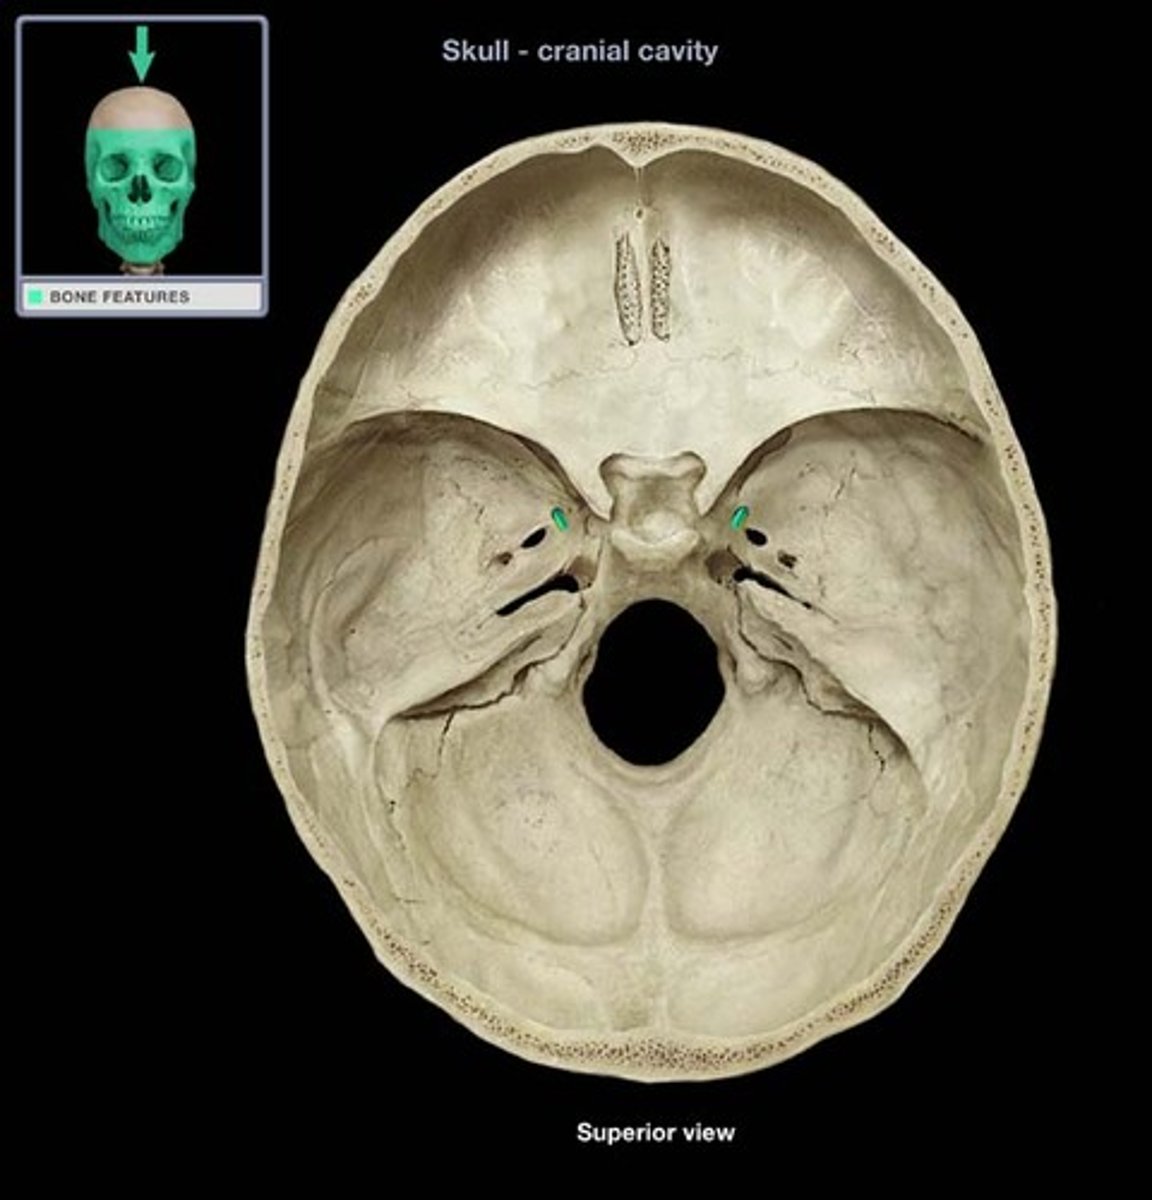

stylomastoid foramen

Name this structure.

carotid canal

jugular foramen

Name this structure.

internal acoustic meatus